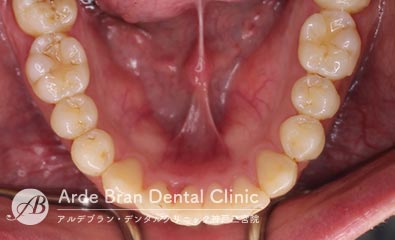

- 鋏状咬合/シザースバイト(20代男性 治療期間10カ月)

- 奥歯のかみ合わせと前歯のがたつきを治したいとの事でご来院されました。なるべく目立たない装置で固定式の装置での治療をご希望されたので、ハーフリンガル矯正にて治療を行いました。奥歯がすれ違って咬んでいる場合はご本人も気づいていない事も多いです。ただこの状態を放置しておくと、歯に大きく負担がかかり歯の寿命が短くなります。今回は上顎の口蓋にインプラントアンカーを植立し、外側に倒れた上顎の奥歯を内側に入れました。患者様より、長年歯並び歯並びが気になっていたので、これからは歯を見せて笑えるのが楽しみです。とのお声を頂きました。

- 治療前

- 治療後

| 装置名 | マルチブラケット装置(ハーフリンガル矯正) |

|---|---|

| 抜歯非抜歯 | 親知らずのみ抜歯 |

| 治療期間 | 10カ月 |

| 費用 | ハーフリンガル矯正83万円+TAX 顎間ゴム500円×数個 |

| リスク副作用 | 装置装着による違和感、歯の移動時の痛み、歯根吸収など。詳しくはこちらをご参照ください。 |